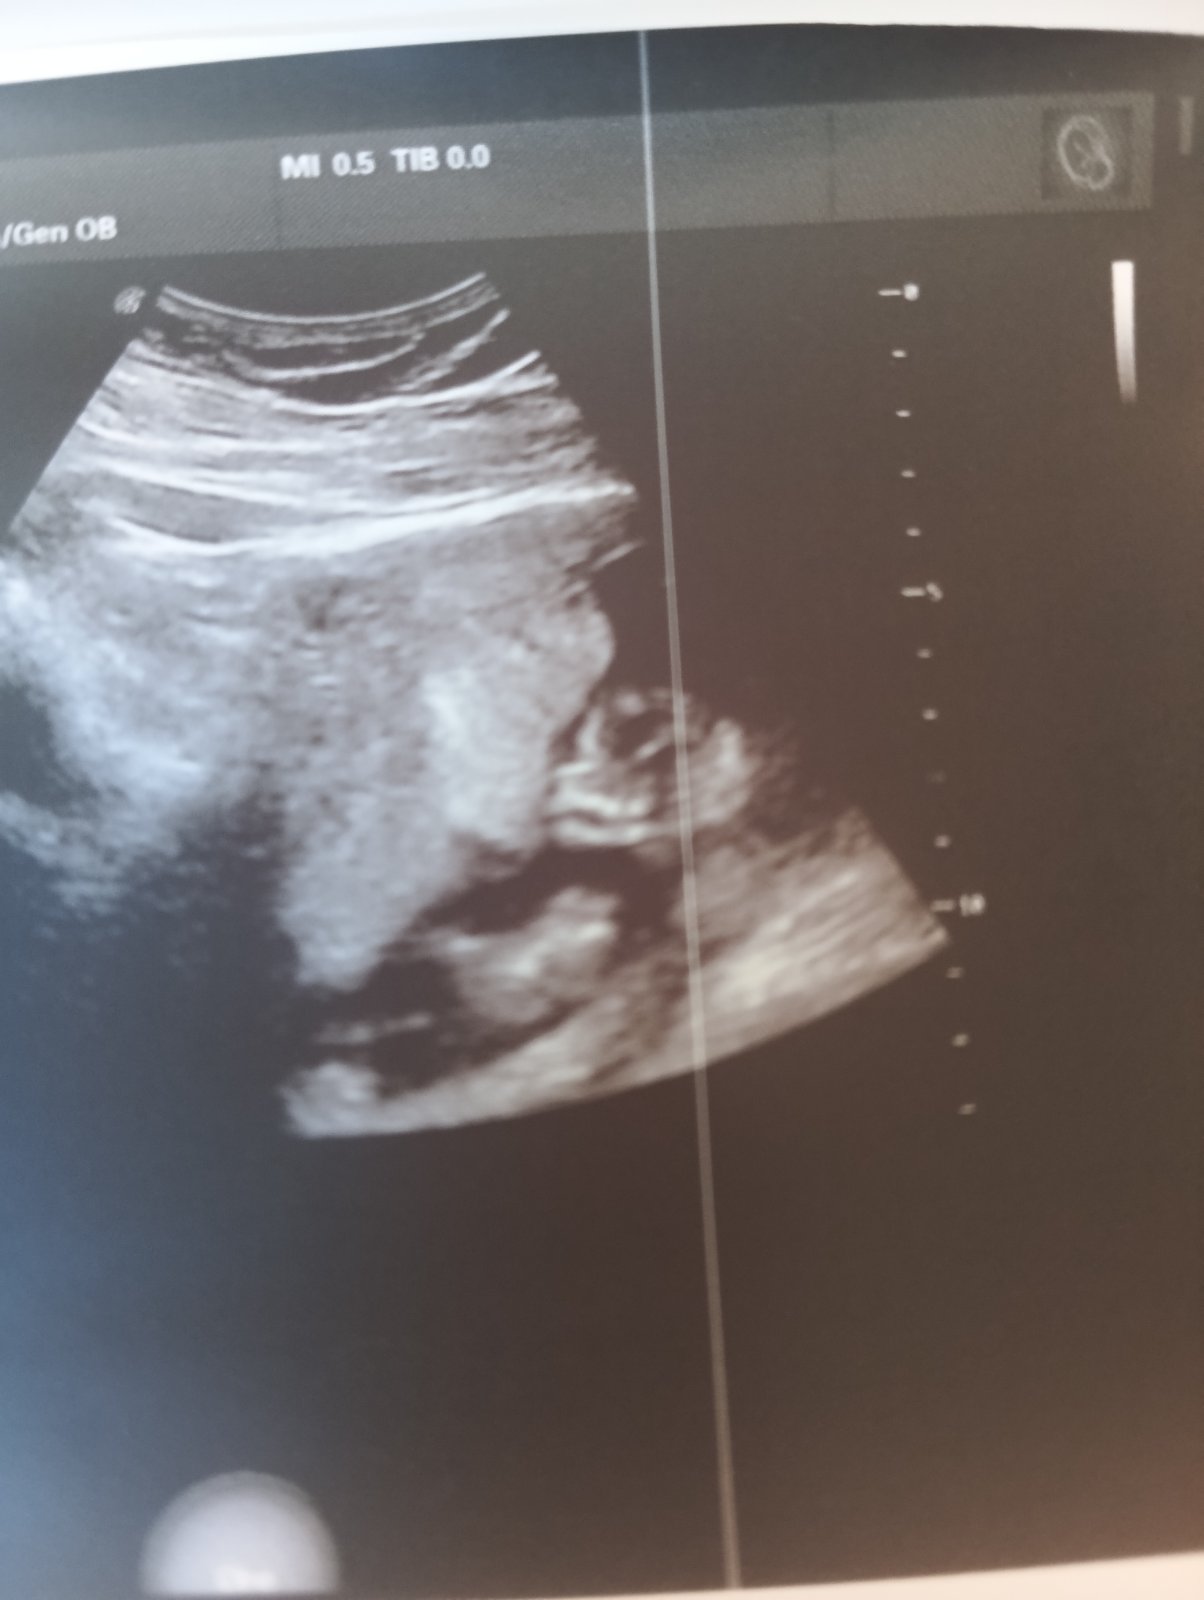

Ahojky všem 🙂 chtěla jsem se ze zajímavosti zeptat , co si myslíte dle fotky ze čekáme je to chlapeček či holčička?je to ult. 13+3 na genetice nám to nechtěli říct ani maličko co si myslejí (víme že to není 100%) ale i tak zvědavost mi nedá 🙂 miminko je pro nás důležité aby bylo zdravé a tak mě zajímá názor ostatních - děkuji 🥰

autorJedinou kterou ještě mám , tak to je tuta a to je 19+8 TT holky

Musela bys dát obyčejnou fotku a z profilu. Z těchhle 3D fotek a z tohoto úhlu se to v tomhle týdnu nepozná.